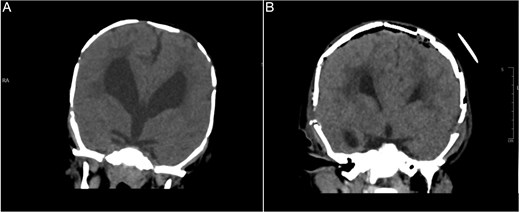

An 11-month-old female infant, born to unrelated Saudi parents, was referred to our facility with unilateral left coronal craniosynostosis, congenital microcephaly, global developmental delay, and a confirmed ZIC1 gene mutation. Comorbidities included a patent foramen ovale, aortopulmonary collateral vessel, G6PD deficiency, and gastroesophageal reflux disease (GERD). At birth head circumference was 29 cm (<first percentile), and progressive skull asymmetry and squinting were noted over time. Developmentally, she exhibited delayed gross and fine motor skills with limited object transfer. On examination, she was alert and visually tracking, with inward ocular deviation (esotropia). Head circumference was 37 cm (<first percentile) with anterior plagiocephaly and towering of the left frontal region (Fig. 1). Pupils were equal and reactive. Fundoscopy and cranial nerve examinations were unremarkable. Gross motor power was within normal limits, except for moderate lower limb spasticity. 3D reconstruction computed tomography (CT) confirmed premature fusion of the left coronal suture with subtle elevation of the superolateral orbital rim, indicating harlequin sign (Fig. 1). Brain CT showed corpus callosum agenesis, colpocephaly, mild ventriculomegaly, right cerebellar and pontine hypoplasia, and a large cisterna magna, consistent with the reported ZIC1-related malformation spectrum (Fig. 2). Given the progressive deformity and concerns of increased intracranial pressure that might be partially contributing to her neurodevelopmental delay, anterior cranial vault expansion with fronto-orbital advancement was performed jointly by the neurosurgery and plastic craniofacial teams (Fig. 3). Intraoperatively, left-sided dural tension was appreciated, indicating localized increased intracranial pressure. The orbital bandeau was reshaped and advanced, achieving immediate cosmetic improvement (Fig. 4). The patient tolerated the surgery well and recovered uneventfully. At her 4-month follow-up, she showed developmental progress including standing without support, purposeful hand use, and verbalization (“Baba”). At 6-month follow-up, brain CT revealed areas of bone resorption which led to the placement of a ventriculo-peritoneal shunt (Fig. 5). The known association of ZIC1 mutation with tethering of the cord prompted spinal magnetic resonance imaging (MRI) screening. Positive findings indicated an untethering procedure, which was successfully done (Fig. 6).

Brain CT bone window illustrating ventriculomegaly and bone resorption at six-month follow-up (A), compared to immediate post operative image (B).